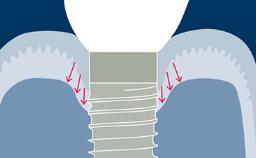

A implantodontia evoluiu consideravelmente desde os protocolos de tratamento precoce, nos quais o posicionamento dos implantes não era considerado crítico para um resultado bem-sucedido. Nesta abordagem orientada cirurgicamente, os implantes foram instalados onde havia osso suficiente para apoiá-los, e a ênfase estava no resultado funcional. Esta imagem clínica mostra três implantes adjacentes suportados por coroas unitárias. Isso proporcionou ao paciente um bom resultado funcional, mas a estética ao nível da emergência do implante foi apenas uma consideração secundária. Na implantodontia moderna, o resultado estético geral é de igual ou maior importância para o paciente. Os resultados estéticos estão intimamente relacionados a um alto nível de precisão no posicionamento dos implantes dentários de suporte. Uma segunda imagem clínica mostra um exemplo de uma coroa unitária implantossuportada no incisivo central superior esquerdo, onde o posicionamento cuidadoso do implante permitiu que o perfil de emergência imitasse o do incisivo central natural. Guias de transferência para orientar a instalação precisa tridimensional do implante são críticos para alcançar esse resultado. Este Módulo de Aprendizado ITI discutirá o uso rotineiro de guias de transferência na implantodontia.